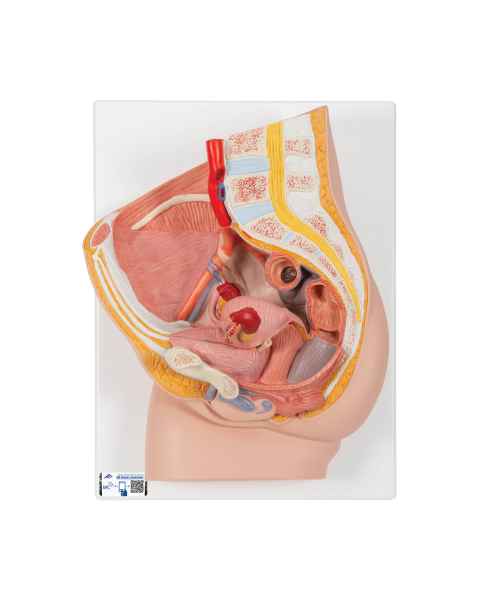

Female anatomical models are an ideal teaching aid to help educate both students and patients. Our extensive selection of female anatomy models includes female pelvic models, pregnancy series models, pelvis skeleton models, delivery/childbirth simulators, clinical breast trainers and self-exam models, uterus/ovary models, and more. Teaching simulators and self-exam models are excellent for educating students and patient education.

For example, the Wearable Breast Self-Exam Model can be easily worn, in order to better train and practice breast self-examination. Our line of prevention and detection models includes the Realistic Left Breast Model, Uterus/Ovary Model with Pathologies, Model of the Female Breast, and the Clinical Breast Trainer. Obstetricians will benefit from owning female anatomy figures of uteri and pelvises with fetuses inside, as well as sets of models that demonstrate the stages of fertilization. Women, particularly first-time mothers, will appreciate having a female education model that clearly illustrates the pregnancy process and what exactly is occurring inside of their body.